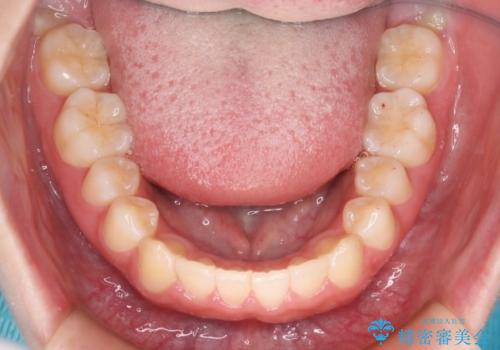

- 前歯のガタつきの改善を主訴に来院された患者様です。

ガタつきによる上顎正中の空隙や歯の突出感も気にされていました。

費用を抑えたいとの事だったので歯の移動量なども考慮し、インビザライン・ライトパッケージでの治療を計画しました。